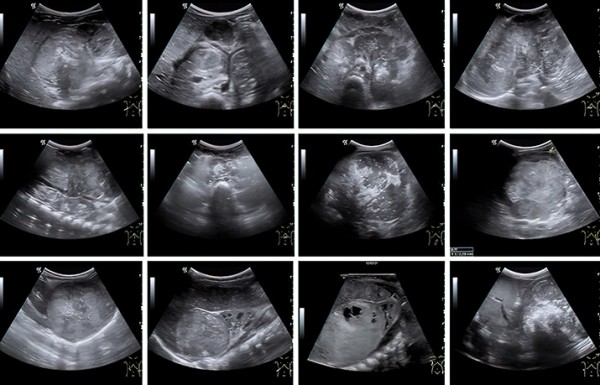

К сожалению, у значительной части пациентов на момент постановки диагноза болезнь уже в распространенной форме. Чаще всего опухоль распространяется в лимфатические узлы, печень, кости и костный мозг (см. рис. 1).

Во время УЗИ на амбулаторном этапе забрюшинная опухоль, как правило, определяется по достижении так называемого диагностического объема в несколько кубических сантиметров. При этом врач уверенно может установить факт наличия образования, его эхоструктуру, чего уже достаточно для направления ребенка на дообследование (см. рис 2).

Рисунок 2. Сонографические варианты нейробластомы.

Наибольшие трудности специалист УЗД испытывает при установлении органной принадлежности опухоли, когда она уже достигла больших размеров. К примеру, медиана диагностического объема впервые установленной нейробластомы у младенца составляет 75 (26–208) см3, а для опухоли почки и того больше — 317 (226–524) см3. Именно эти новообразования приходится дифференцировать, в том числе и в онкологическом центре, т. к. химиотерапевтическое лечение опухоли Вильмса в ряде случаев начинают по результатам диагностики на основе визуализирующих методов исследования.